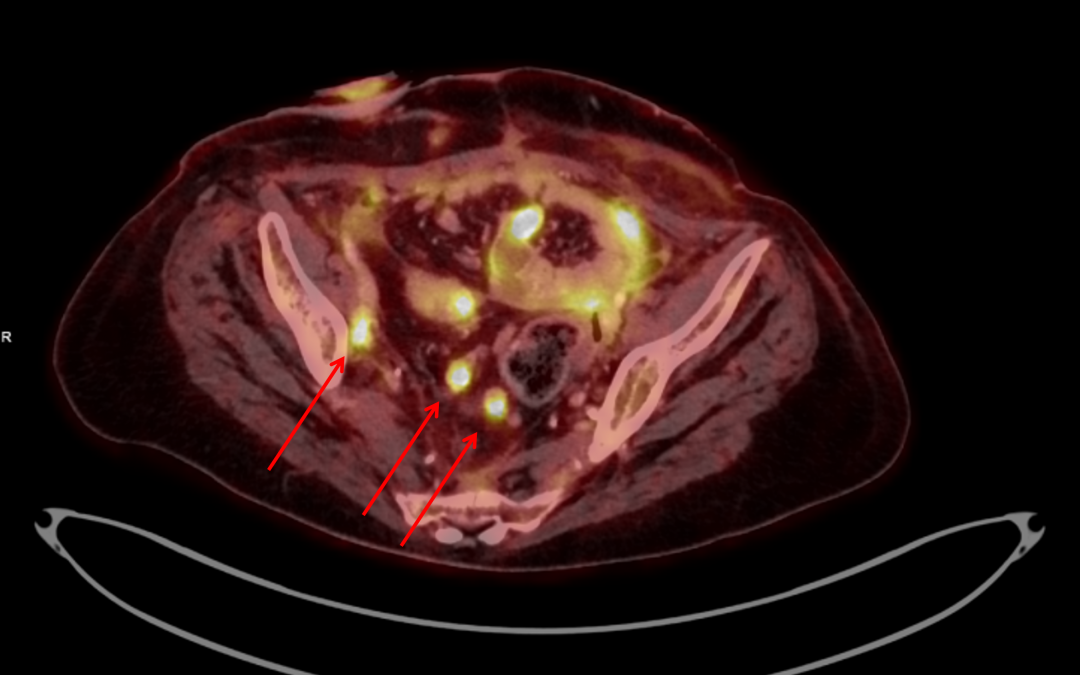

Breast Implant- Associated Anaplastic Large Cell Lymphoma: FDG PET/CT imaging Figure 1: Mild-moderate uptake in peri-capsular effusion in the left breast. Figure 2: mild uptake in an axillary lymph-node, considered to be reactive. Figure 3: No pathological FDG...